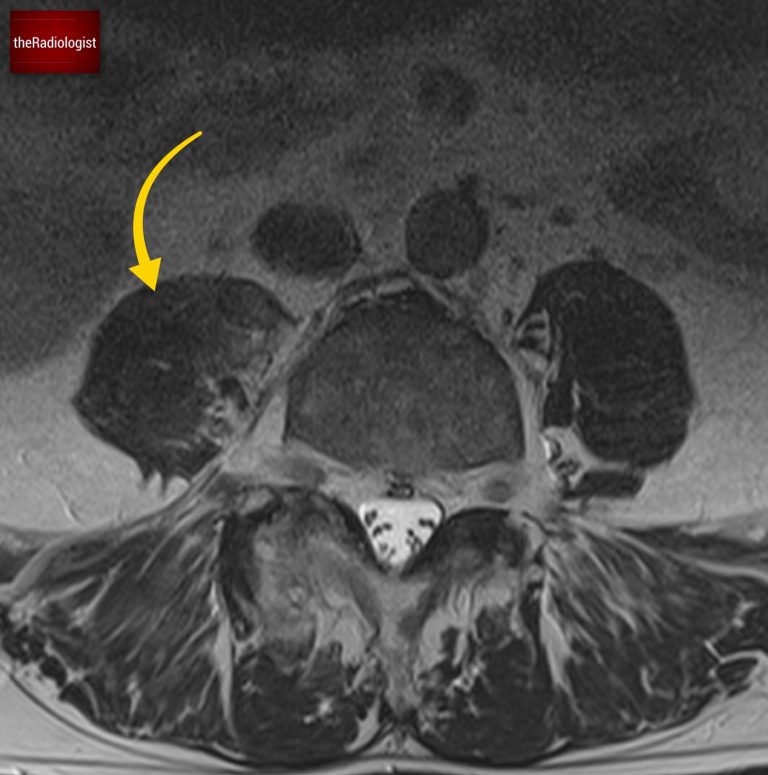

If we look at a lateral STIR sequence of the lumbar spine, we can see high signal in the lateral aspect of the L3-4 disc which is continuous with the abscess formation within the right psoas. This highly suggests a spondylodiscitis as the primary pathology leading to secondary psoas abscess.

High signal within the lateral aspect of the L3-4 disc is continuous with abscess formation.